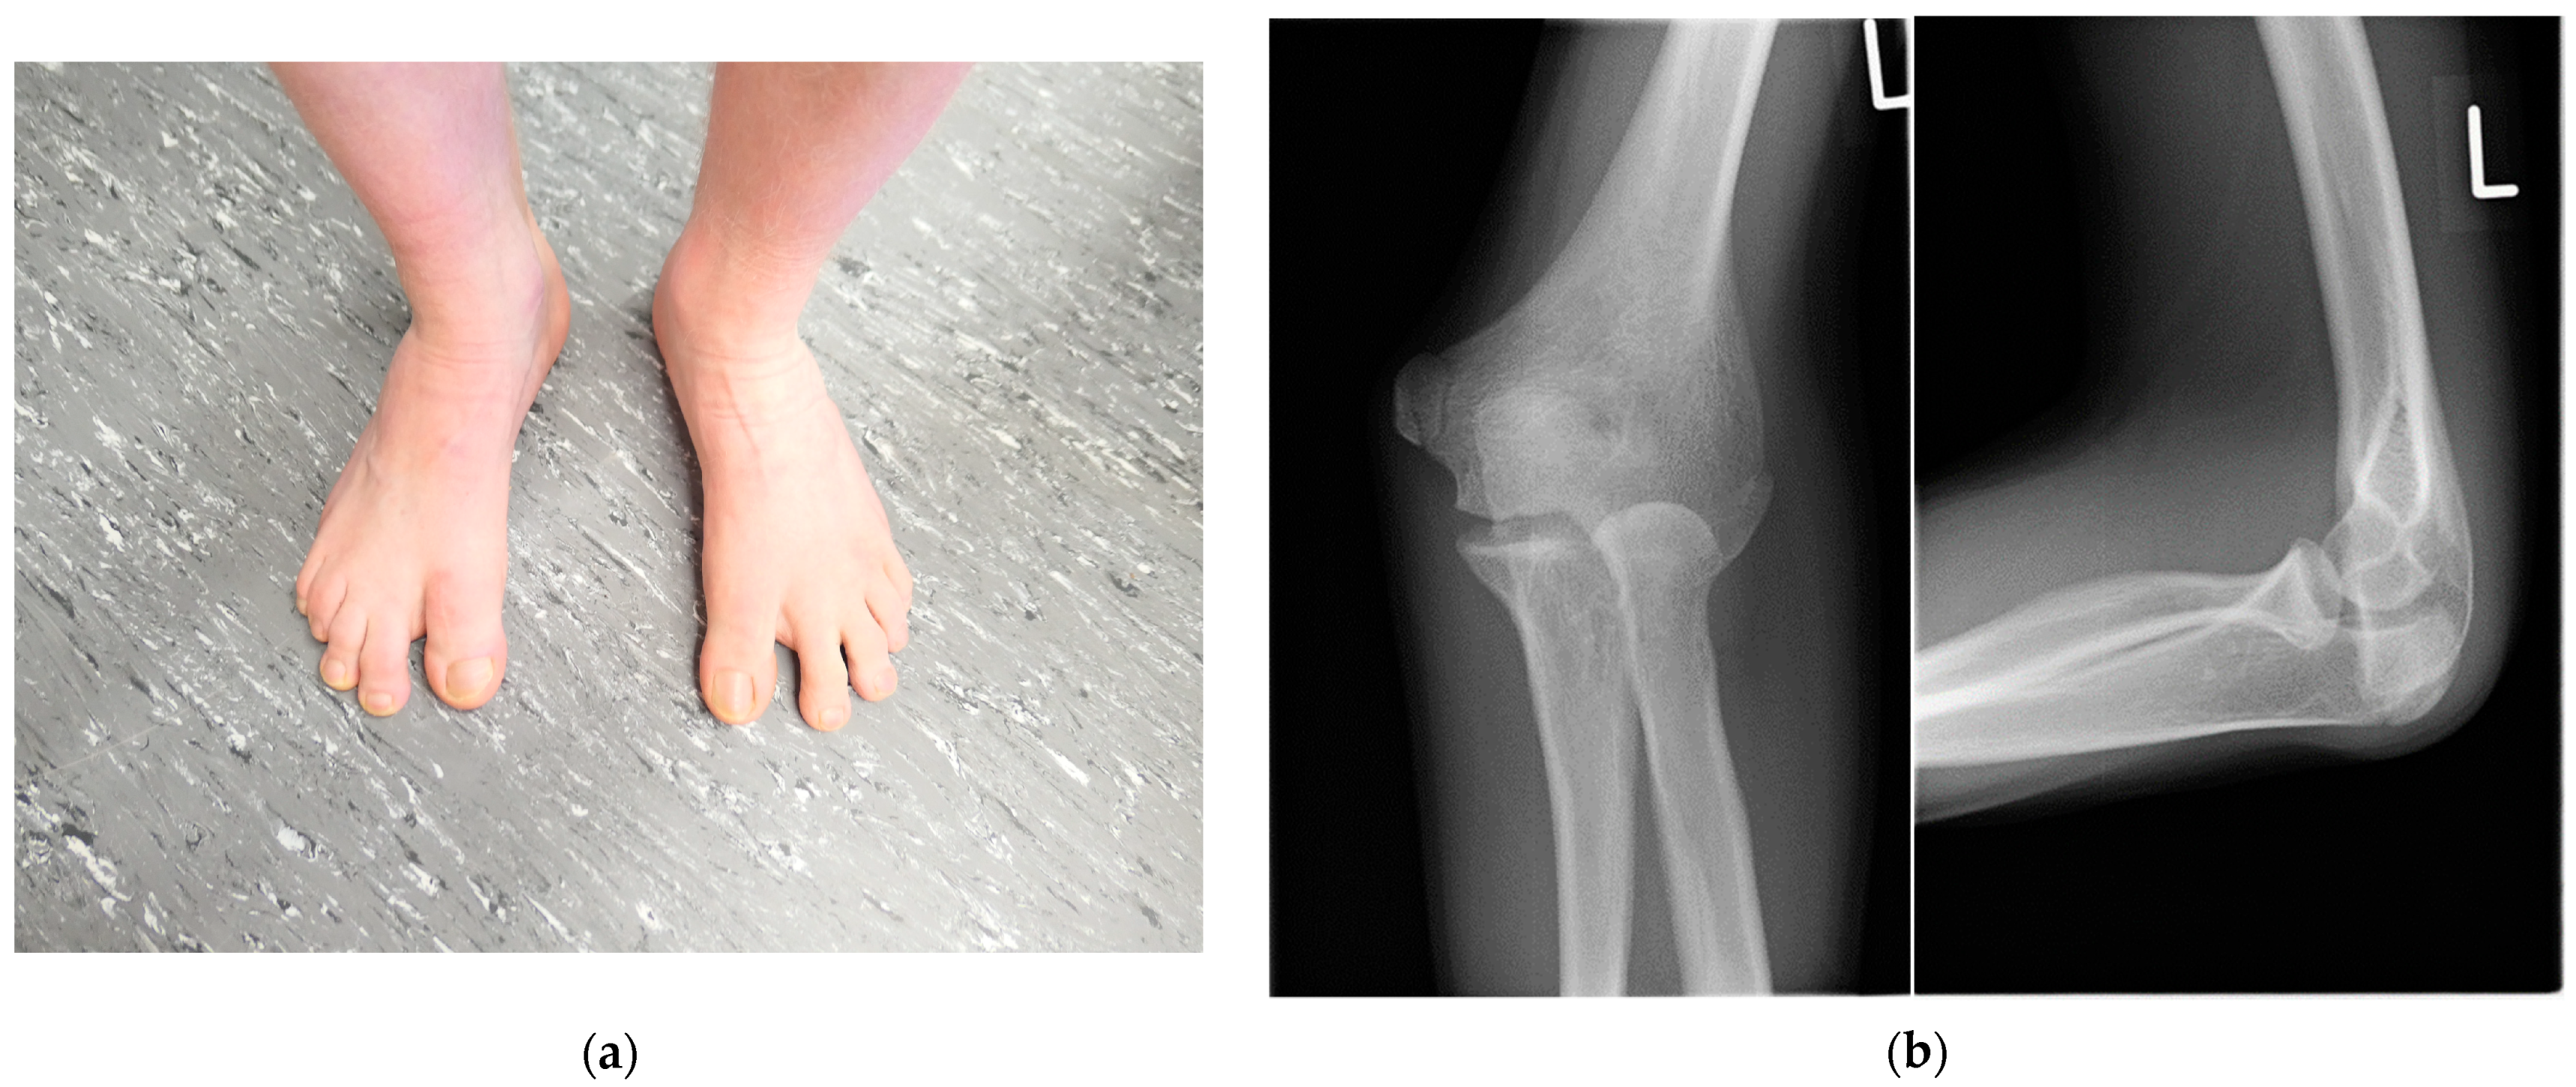

| Anomaly of elbow joint | + | + | + | 26/26 | 12/12 | 0/2 | 1/1 | 0/1 | 1/1 | 1/1 | 44/47 (94%) |

| Synostosis of feet | - | + | - | 9/26 | 8/12 | 1/2 | 1/1 | 1/1 | 1/1 | 1/1 | 23/47 (49%) |